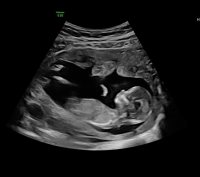

12+5 (målt til 13+0) i går, alt bare vel der inne :love017 Jordmor var veldig sikker på at den lille krabaten er ei jente:Heartred